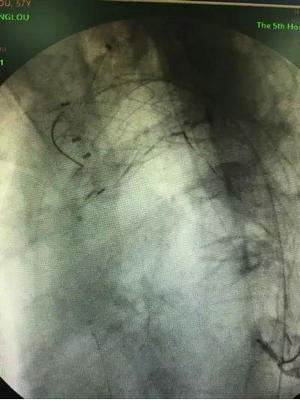

植入分支支架,左锁骨下动脉通畅,无明显内漏

手术设计巧妙,过程顺利,王兵教授主刀,崔文军副主任等医师密切配合,整个手术过程仅耗时2小时。复查造影显示主动脉支架位置良好,破口封堵满意,无内漏,左锁骨下动脉支架通畅,无脑梗塞、肢体及内脏缺血等并发症的发生。整个手术过程中,胡强夫教授带领麻醉团队严格控制血压、心率水平,为手术保驾护航,术后在施敏护士长带领的护理团队精心的护理下,患者恢复良好。